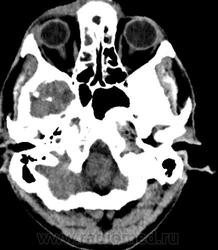

- тотальное снижение пневматизации обоих половин лобных пазух, обоих гайморовых пазух, передней и средней групп ячеек решетчатого лабиринта с двух сторон патологическим содержимым плотностью +17+23HU. Устья гайморовых пазух блокированы патологическим субстратом.

По задней стенке правой половины лобной пазухи определяется выбухание патологического содержимого в полость передней черепной ямки с наличием реактивного утолщения надкостницы ~на 5 мм. При контрастном усилении наблюдается интенсивное накопление контрастного вещества толстой стенкой отграниченного образования, содержимое пазух не накапливает контрастный препарат.

Также определяется канал со склеротическим контуром, сообщающийся с полостью левой гайморовой пазухи и полостью рта, шириной 1,7 мм являющийся ороантральным свищом;

Заключение: КТ признаки полисинусита, осложненного хроническим остеомиелитом стенок гайморовых и обоих половин лобной пазухи, ячеек решетчатого лабиринта справа, наличием участков деструкции стенок обоих половин лобной пазухи, зоны энцефалита в полюсно-базальных отделах правой лобной доли. Полипы передне-верхней стенки левой половины основной пазухи, среднего носового хода справа. Признаки ороантрального свища слева.